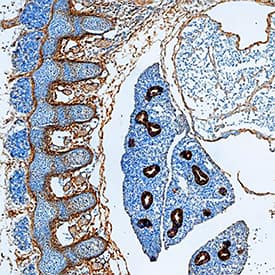

Detection of P-Cadherin in Human Liver.

P-Cadherin was detected in immersion fixed paraffin-embedded sections of human liver using Goat Anti-Mouse P-Cadherin Antigen Affinity-purified Polyclonal Antibody (Catalog # AF761) at 0.5 µg/ml for 1 hour at room temperature followed by incubation with the Anti-Goat IgG VisUCyte™ HRP Polymer Antibody (Catalog #

VC004). Before incubation with the primary antibody, tissue was subjected to heat-induced epitope retrieval using VisUCyte Antigen Retrieval Reagent-Basic (Catalog #

VCTS021). Tissue was stained using DAB (brown) and counterstained with hematoxylin (blue). Specific staining was localized to the cell membrane of hepatocytes. View our protocol for IHC Staining with VisUCyte HRP Polymer Detection Reagents.